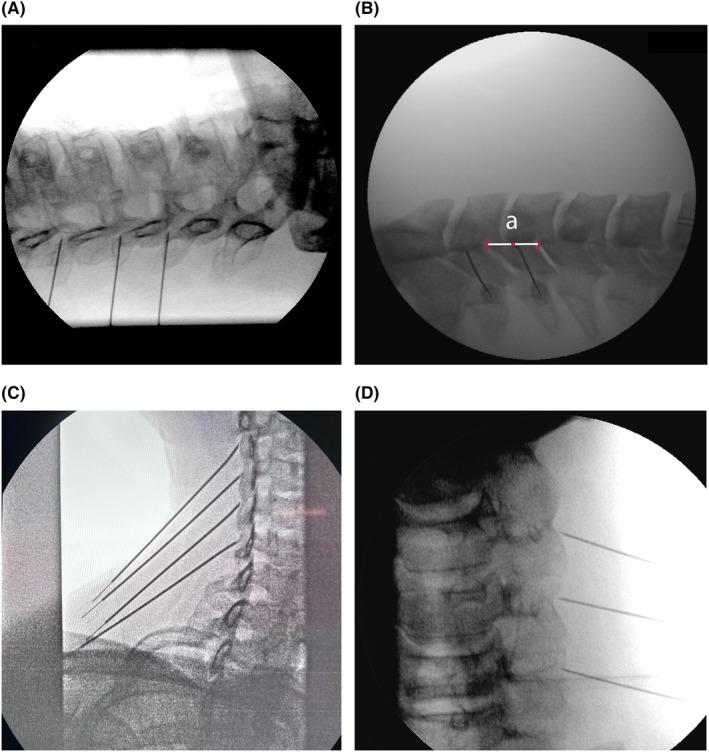

Facet-related pain is typically diagnosed based on history and physical examination of the patients, combined with a diagnostic block (eg, with local anesthetic) of the medial branches innervating the joints. There is no additive value for imaging techniques to diagnose cervical facet pain, but imaging may be used for procedure planning. First-line therapy for pain treatment includes focused exercise, graded activity, and range-of-motion training. Pharmacological treatment may be considered for acute facet joint pain; however, for chronic facet joint pain, evidence for pharmacological treatment is lacking. Considering the lack of evidence for treatment with botulinum toxin, intra-articular steroid injections, or surgery, these interventions are not recommended. Diagnostic blocks are not considered a viable treatment option, though some patients may experience a prolonged analgesic effect. Long-term analgesia (>6 months) has been observed for radiofrequency treatment of the medial branches.

小关节相关疼痛通常根据患者的病史和体格检查,结合对支配关节的内侧支进行诊断性阻滞(如使用局部麻醉剂)来诊断。成像技术对诊断颈椎小关节疼痛没有附加价值,但成像可用于手术规划。疼痛治疗的一线疗法包括针对性锻炼、分级活动和活动范围训练。急性小关节疼痛可考虑药物治疗;然而,对于慢性小关节疼痛,缺乏药物治疗的证据。考虑到肉毒杆菌毒素、关节内注射类固醇或手术治疗缺乏证据,不推荐这些干预措施。诊断性阻滞不被视为可行的治疗选择,尽管一些患者可能会有延长的镇痛效果。内侧支射频治疗已观察到长期镇痛(>6个月)。